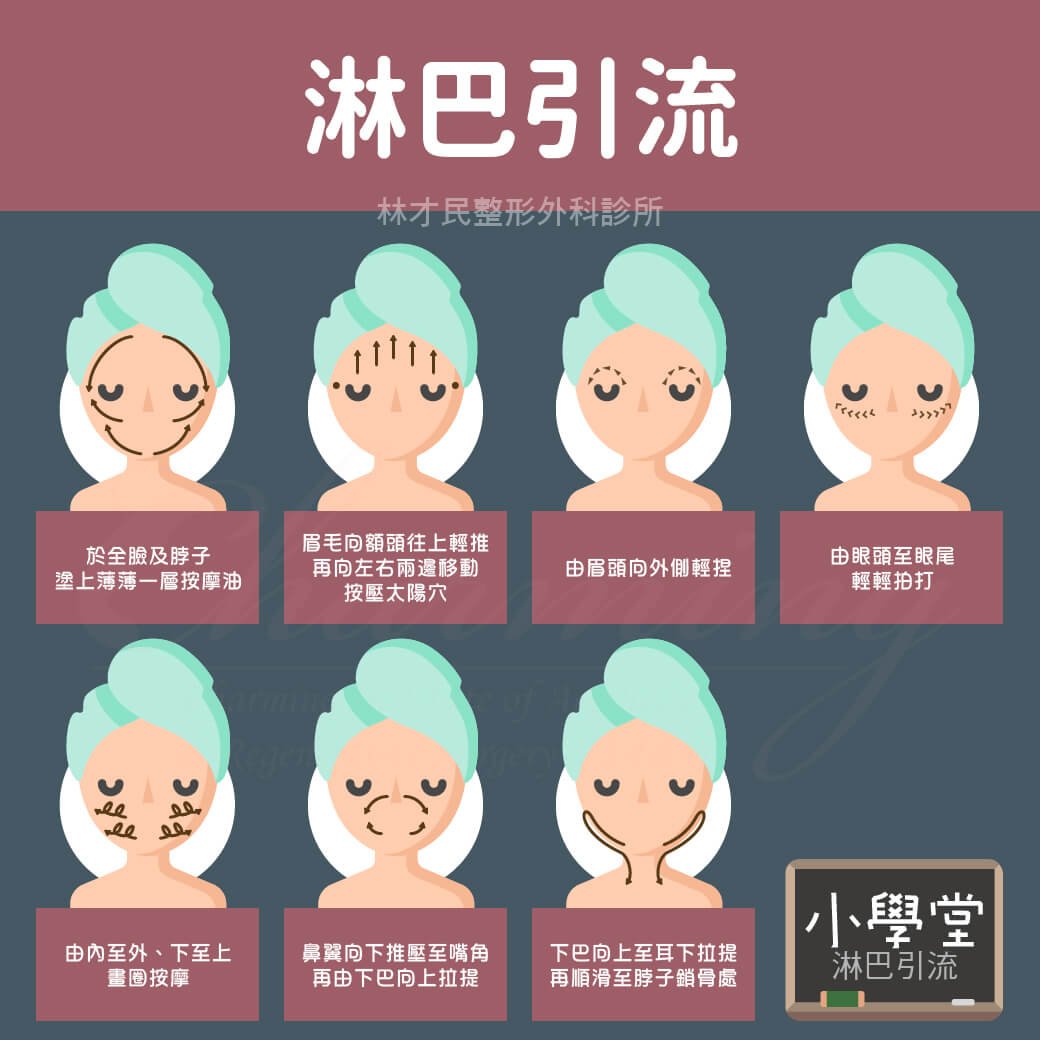

【小學堂】肌膚保養 淋巴引流 | 林才民整形外科診所CIARS